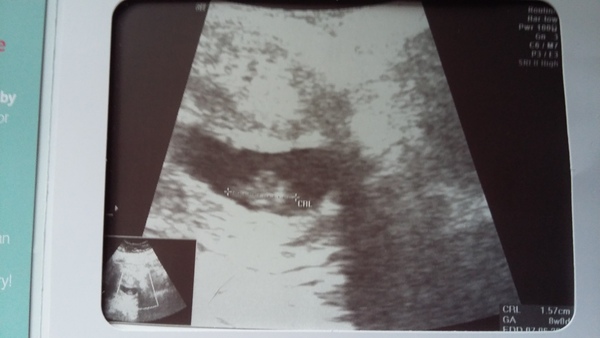

What a day, woke up this morning with NO symptoms, not even a sore boob, slept right through last night without needing a wee, convinved myself it was all over then had brown mucus spotting as well. Rung EPU for advice and all is well, phew! Got to see heartbeat Smile picture quality is very poor probably due to my high BMI I imagine Blush

So sorry you had brown my as have so glad all is well and what a lovely scan photo!!'

Lovely pic haveacup so glad all is well!